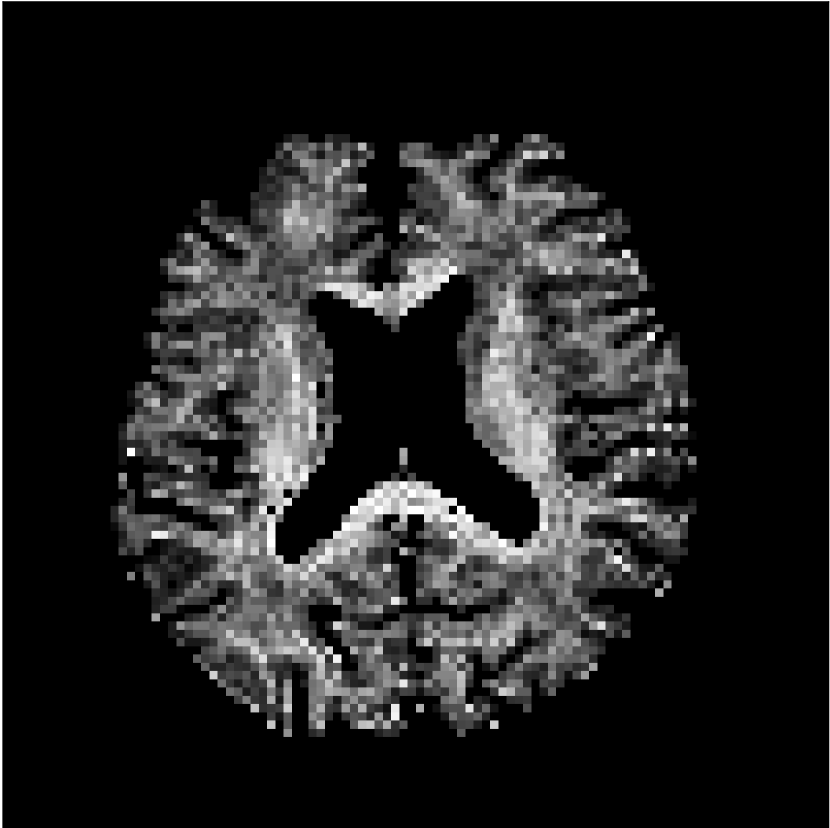

Figure 8 shows examples of non-diffusion-weighted images before and after processing. The raw images (Raw) served as the input for the magnitude deep learning (MCNN) and complex deep learning (CCNN) methods.

Raw 𝐱tsubscript𝐱𝑡\mathbf{x}_{t}

MCNN, fθ^(𝐱t)subscript𝑓^𝜃subscript𝐱𝑡f_{\hat{\theta}}\left(\mathbf{x}_{t}\right)

MCNN Resid., Ric(𝐱t)fθ^(𝐱t)Ricsubscript𝐱𝑡subscript𝑓^𝜃subscript𝐱𝑡\text{Ric}(\mathbf{x}_{t})-f_{\hat{\theta}}\left(\mathbf{x}_{t}\right)

CCNN, fθ^(𝐱t)subscript𝑓^𝜃subscript𝐱𝑡f_{\hat{\theta}}\left(\mathbf{x}_{t}\right)

CCNN Resid., Ric(𝐱t)fθ^(𝐱t)Ricsubscript𝐱𝑡subscript𝑓^𝜃subscript𝐱𝑡\text{Ric}(\mathbf{x}_{t})-f_{\hat{\theta}}\left(\mathbf{x}_{t}\right)

No PF

5/8 PF

Figure 8: Examples of non-diffusion-weighted images from in vivo data at b=0𝑏0b=0 s/mm2. Artifacts in the Raw image, 𝐱tsubscript𝐱𝑡\mathbf{x}_{t}, are corrected by the MCNN and CCNN models, fθ^(𝐱t)subscript𝑓^𝜃subscript𝐱𝑡f_{\hat{\theta}}(\mathbf{x}_{t}). Also shown are the residuals between the CNN corrections and the original Raw image with Rician bias correction Ric(𝐱t)Ricsubscript𝐱𝑡\text{Ric}(\mathbf{x}_{t}) [10]. The Gibbs artifacts removed by the methods are observed in the residuals. The MCNN method introduces some banding artifacts at the PF 5/8ths factor that are not present in the CCNN method.

Both methods remove artifacts, but the MCNN method allows residual rippling artifacts to pass through in the presence of partial Fourier. These rippling artifacts are not present in the CCNN method.